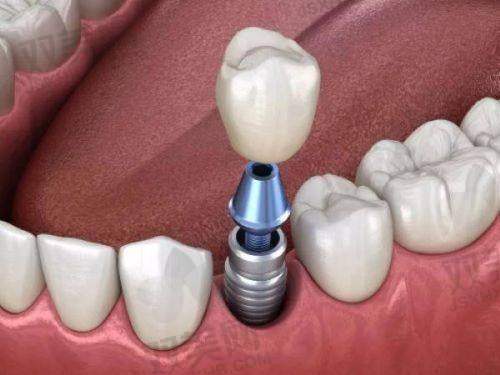

2. **牙齿种植**:采用精良的种植技术和优质的种植体,为缺失牙患者提供安心、有效的种植修复方案,修复牙齿的咀嚼功能和美观。

2. **个性化治疗方案**:医生会根据每个患者的口腔状况、需求和期望,制定个性化的治疗方案。在牙齿正畸方面,会综合考虑患者的牙齿排列、咬合关系、面部形态等因素,选择更适合的矫正方法;在牙齿种植方面,会根据患者的牙槽骨条件、缺失牙情况等,选择合适的种植体和种植方案。这种个性化的治疗方案能够更好地满足患者的需求,提高治疗成效。

3. **优质的材料**:医院在治疗过程中使用的都是优质的口腔材料,如正畸托槽、种植体、牙齿美白剂等。这些材料具有良好的生物相容性和稳定性,能够确保治疗的安心性和有效性。例如,种植体采用的是国内外有名品牌的产品,具有良好的骨结合能力,能够确保种植体的长期稳定;牙齿美白剂则是经过严格检测的安心产品,能够在不损伤牙齿的前提下达到理想的美白成效。